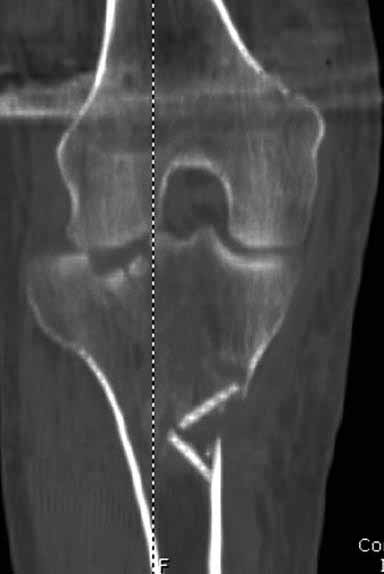

Здравствуйте уважаемые коллеги!Сегодня обратился больной 35л. Травму получил 3 мес.назад, упал в яму, лечился в отдаленном районе гипсовой повязкой, 1 месяц назад гипс сняли , и больной начал ходить с нагрузкой, постепенно появилась деформация коленного сустава, неустойчивость и боли. Локально: деформация коленного сустава, голень смещена кзади- типа подвывиха, разгибание 170гр. Сгибание 150гр.симптомов повреждение коллатеральных и крестообразных связок определить не удается из-за боли и контрактуры. Первичных снимков пока нет, обещали принести, имеется снимки через 2 месяца после травмы без гипса, недельной давности снимки в прямой проекции и К Т. Похоже, что импрессия переднемедиальной части внутреннего мыщелка б/берцовой кости, отрыв межмыщелкового возвышения.

На снимке типичный перелом медиального тибиал плато с передним смещением (подвывих) по Schatzker IV. Консервативное лечение без медиальной опоры не может удержать деформирующие силы, и из-за вторичного смещения мыщелка конечность смещается в варус. Кроме передних смещений еще встречаются сложные фронтальные варианты переломов, и тогда голень подвывихивается кпереди.

А в данном случае мыщелок сросся со смещением кпереди и ротирован. За счет интактной наружной колонны опороспособность конечности сохранена, но остается варус и экстензия конечности. Для предоперационного расчета необходимо сделать на всю длину конечности рентгенограмму, а в остром периоде КТ и 3-мерный снимок помогут лучше ориентироваться в характере перелома.